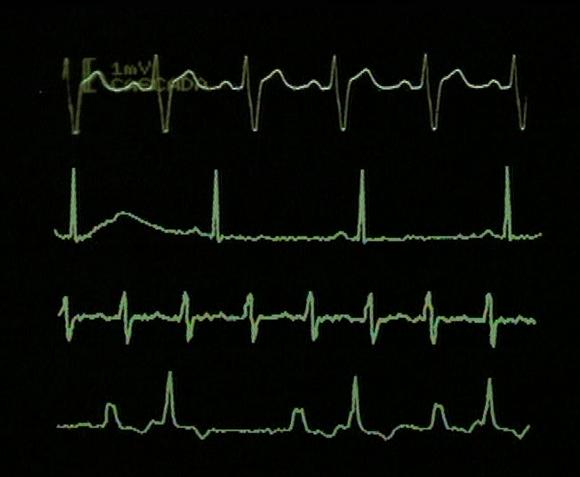

GRÁFICAS DEL CORAZÓN.

b) Un electrocardiograma.

LAS VARIABLES DE UN ELECTROCARDIOGRAMA.

En el eje vertical de la anterior se representa la de potencial de los impulsos eléctricos del corazón. En el eje horizontal el medido en .

¿Qué tipos de latidos puede tener nuestro corazón?